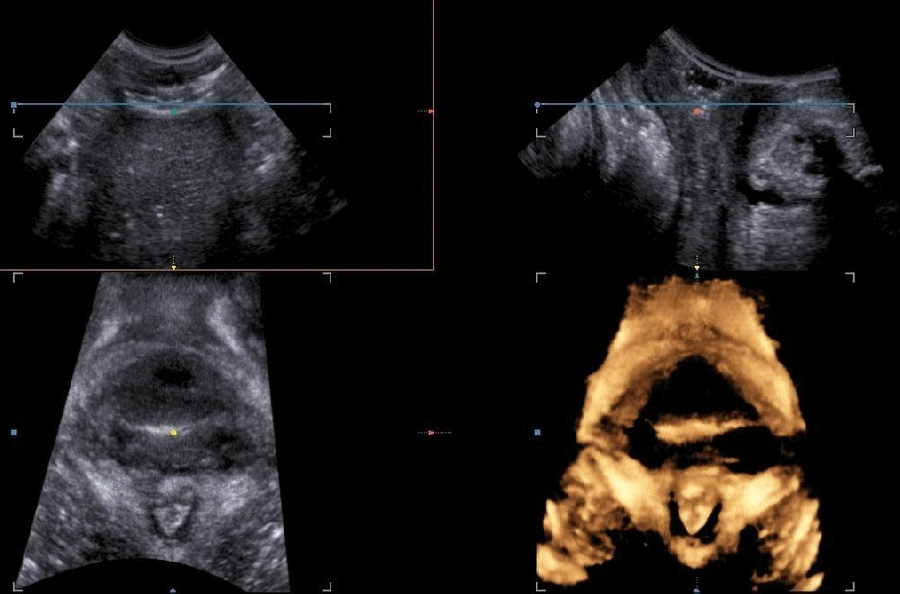

The levator ani muscle avulsion may be demonstrated with 2D Ultrasound, however 3D (or even 4D) Ultrasound as well as MRI are superior in demonstrating avulsion (Dietz 2019).